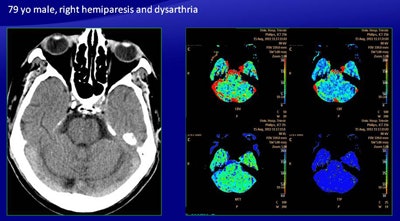

As for the automatically generated maps, among the 19 patients with follow-up CT, seven had no perfusion abnormalities (two true negatives, five false negatives), while 12 patients had perfusion abnormalities. There were 25 areas of perfusion deficit: 15 were compatible with ischemic penumbra and 10 were compatible with infarcted tissue, with a total of 12 true-positive cases.

For the automatically generated maps, sensitivity was 70%, positive predictive value was 100%, specificity was 100%, and negative predictive value was 28%.

For infarcted tissue, in four of 14 cases there was a discordance -- all true positive on the manually generated maps and all false positive on the software generated maps. These included three false positives in the basal ganglia. There was also one false negative produced by the software.

"There was an area of reduced CBV, reduced CBF, and increased MTT in the left pons, suggesting an infarction of the pons, but the color map showed only abnormalities, leading to a false negative revealed in the follow-up CT, which showed a large infarct in the pons," Ukmar said.

The automatically generated maps had lower sensitivity than the manually generated ones, particularly in the infratentorial area and the basal ganglia area. The automated scheme also tends to underestimate the extent of perfusion of the ischemic penumbra.